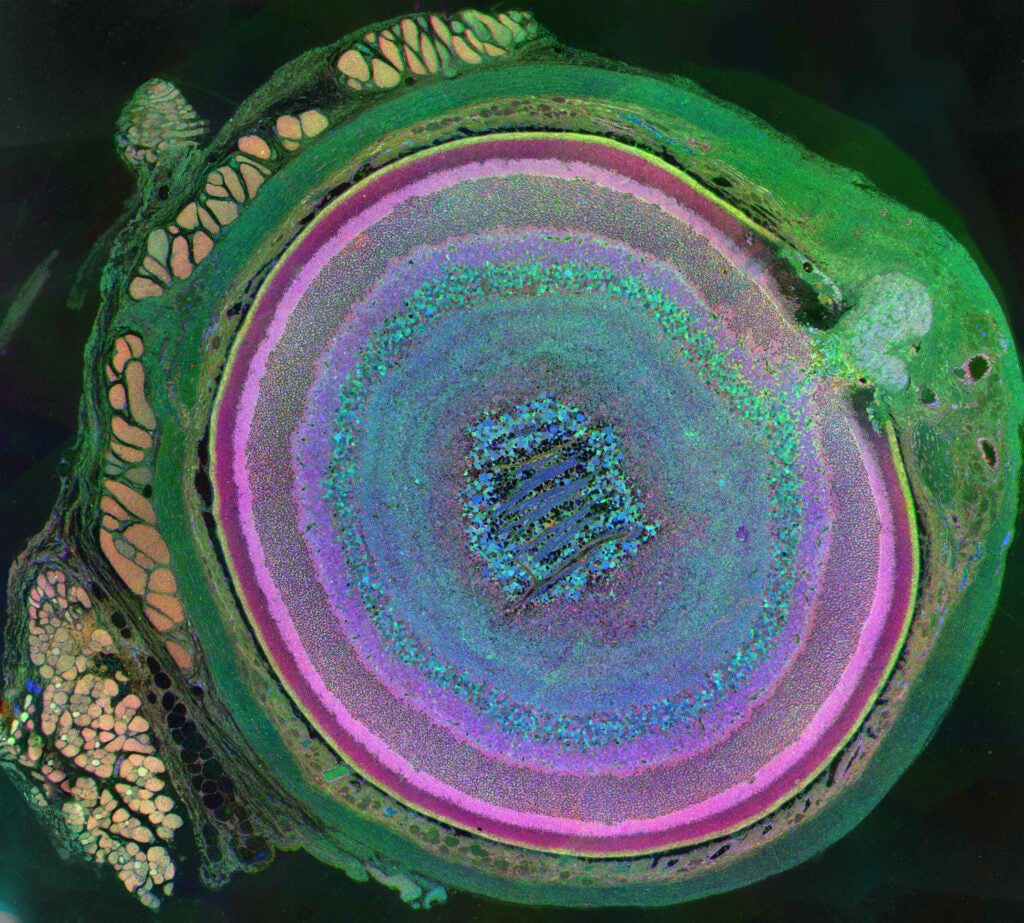

Photography First Place – Metabolomic Eye

This is a metabolic snapshot of the diversity of cells in a mouse eye, and the first-place winner for photography in the 2011 International Science and Engineering Visualization Challenge. The image was derived using a technique called computational molecular phenotyping (CMP). The optic nerve head can be seen in the upper right portion of the image with the rectus muscles (red/gold) attaching to the sclera (green) on the upper left portion, and an oblique muscle in the lower left. Concentric rings of retinal layers are then represented from the sclera through to the vascular choroid to the optic fiber layer.